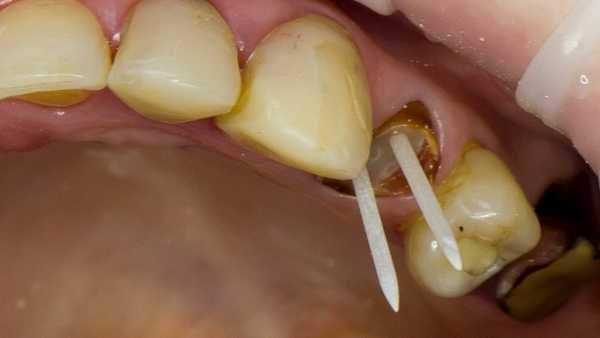

После этого осуществляется установка стекловолоконного штифта Luxapost (DMG)

(Рис.5)

Установка стекловолоконного штифта

Корневой канал обрабатывается адгезивом химического отверждения Luxabond (DMG). Затем наконечником для смешивания Colibri plus (Sulzer MIXPAC) вносится материал Luxacore Z (DMG).